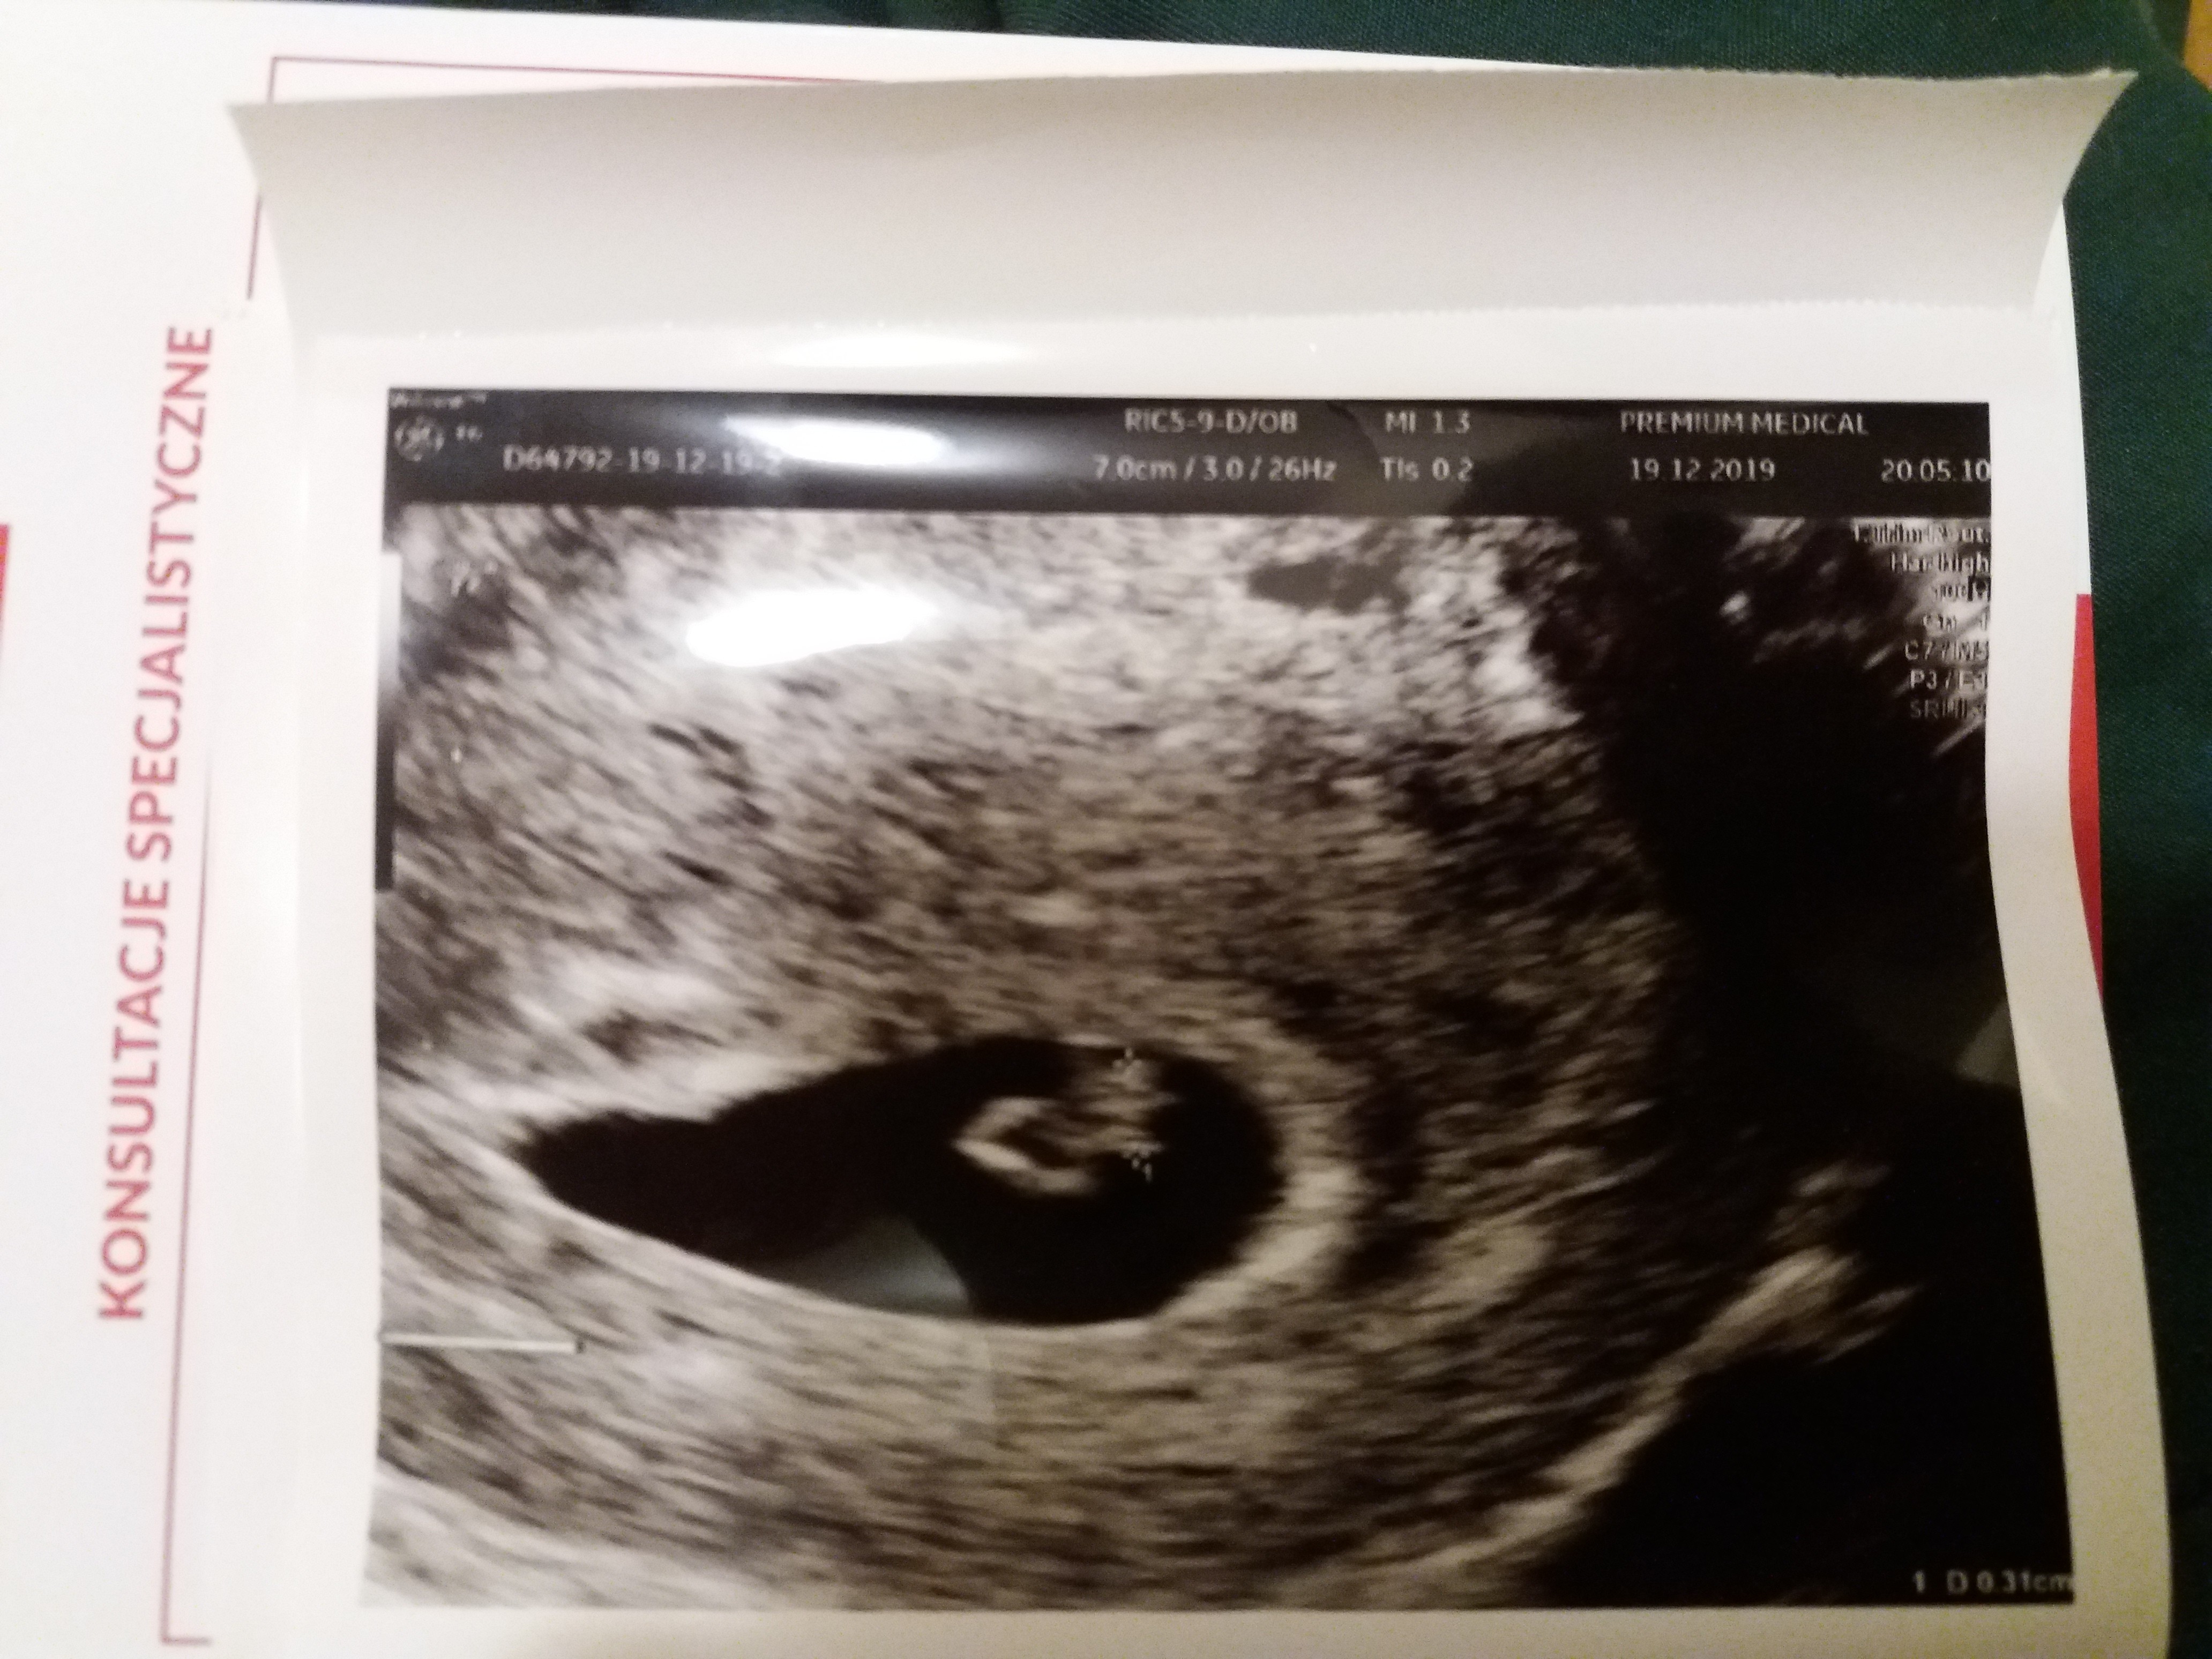

Hej dziewczyny, dawno mnie nie było, męczył mnie rotawirus, ale już jest dobrze. Dzisiaj 6+6, jest piękne serduszko, malec rośnie, wszystkie zlecone badania w porządku, progesteron wysoki. Leciutkie mdłości i zmiany apetytu co chwilę :) nic tylko cieszyć się ciążą.

Taki maciupki 😄

• 20191219_210649.jpg

1,8 MB · Wyświetleń: 113